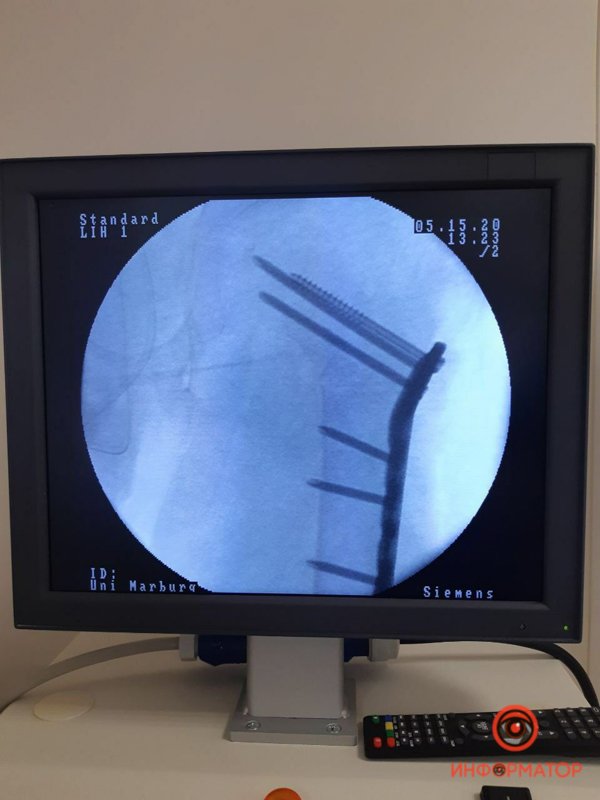

"9 мая к нам доставили мальчика с задержкой в развитии из Никополя. У ребенка случился эпилептический приступ, когда он сидел в "позе лотоса". Как следствие - сломал 2 шейки бедренной кости. Его прооперировали в пятницу по современной методике (открытая репозиция, остеосинтез LCP- пластиной) - сразу выполнено лечение двух бедер. Мальчик уже в палате, без гипсовых повязок, во вторник поедет домой", - рассказал Дмитрий Ершов.

Врач добавил, что обычно такие повреждения лечатся длительным скелетным вытяжением, после чего 2-3 месяца пациент должен пребывать в гипсовой повязке. Малыш же получил современное хирургическое лечение, после которого ему понадобится лишь реабилитация для возвращения способности к ходьбе. Случай такого лечения - крайне редкий, в мировой литературе есть лишь несколько подобных примеров, отмечает врач.